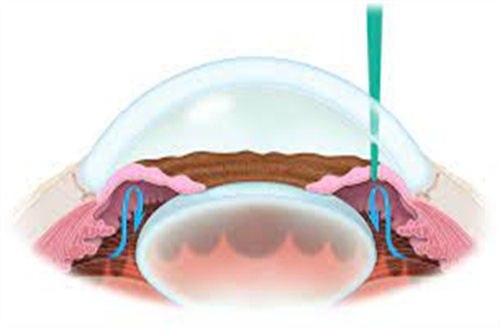

青光眼小梁切除术:5200元起